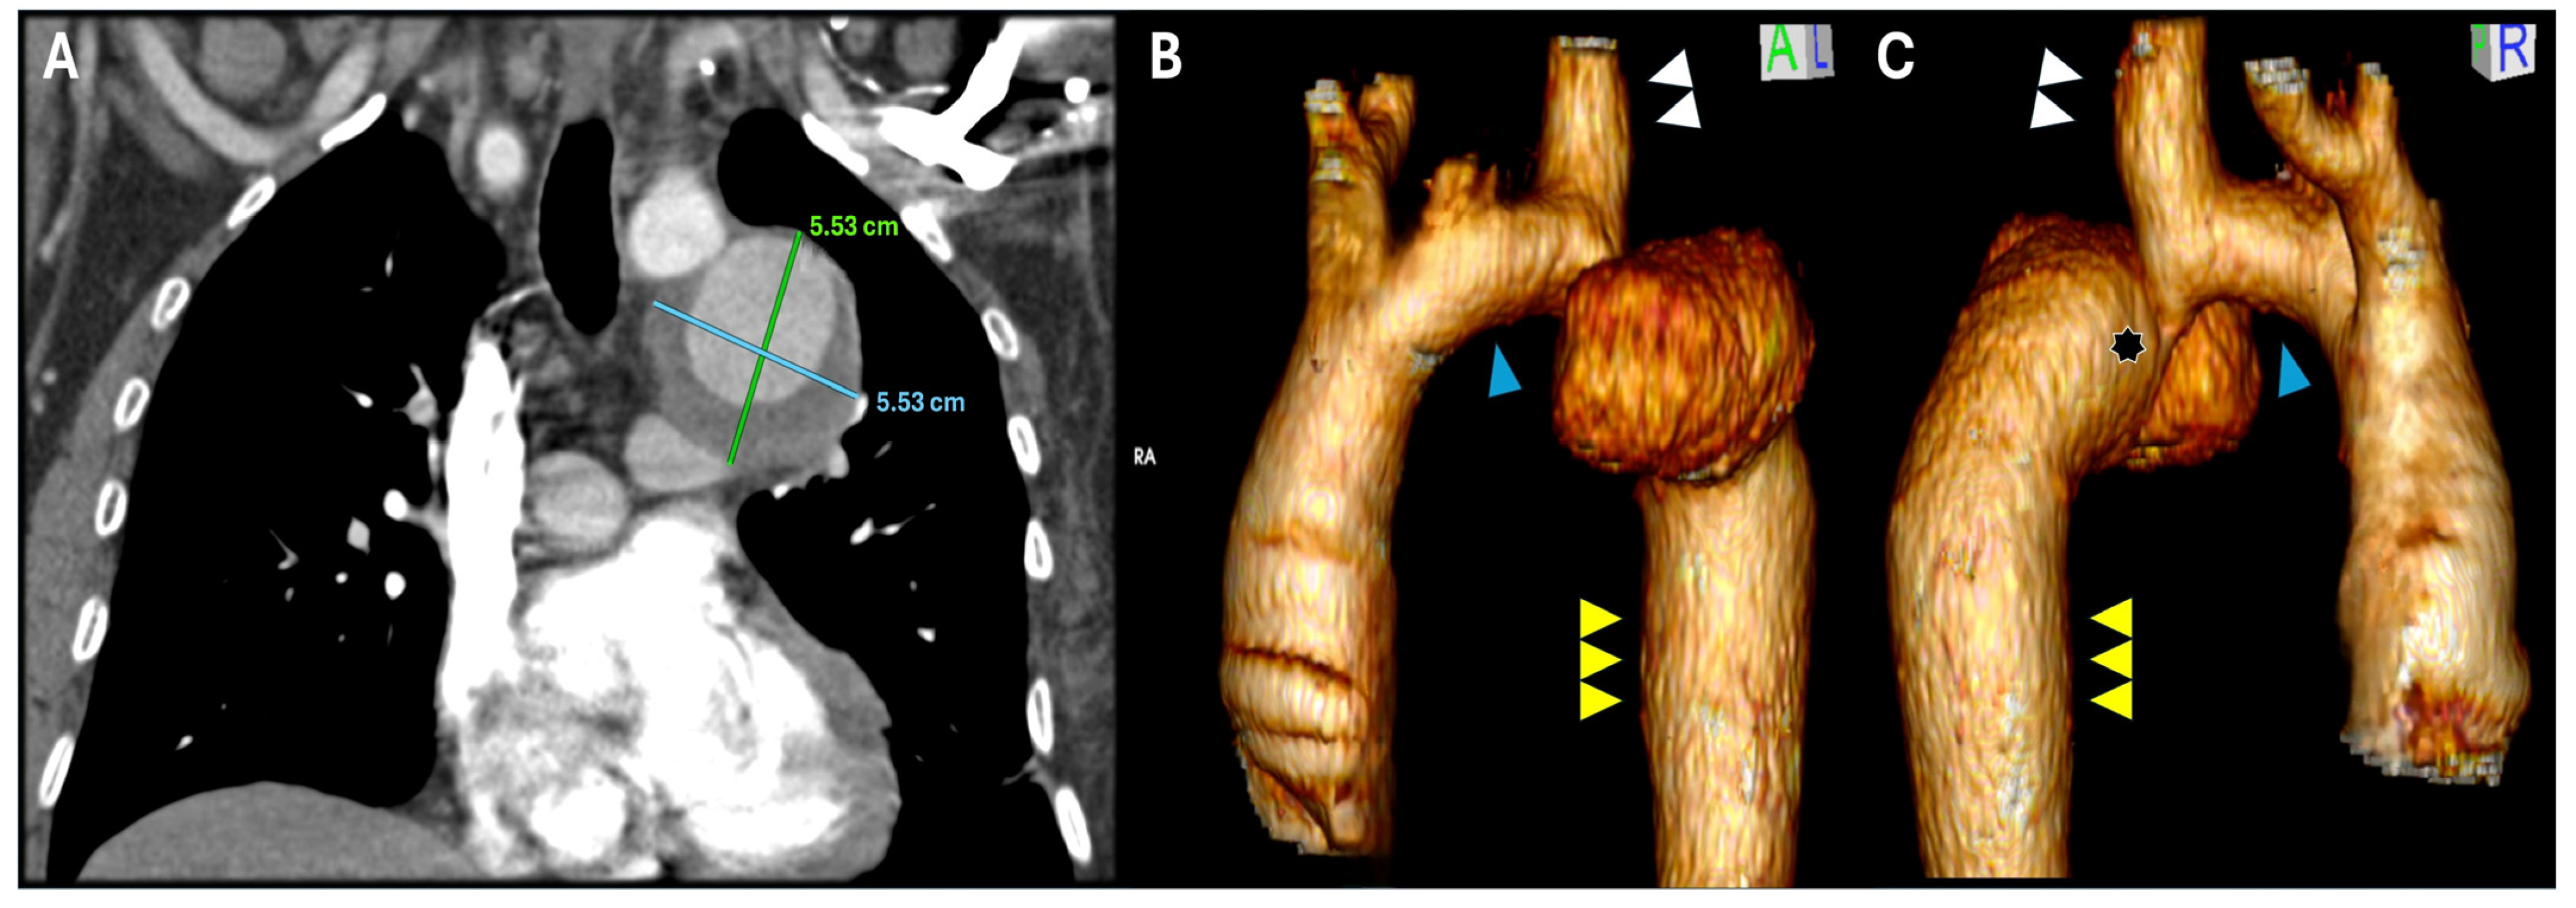

2. Case Report Description